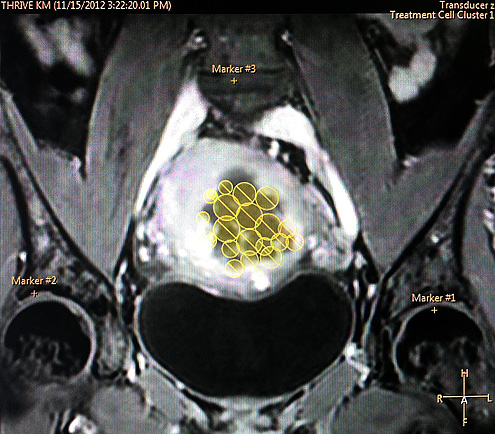

Seitens der Gynäkologie werden operative (Myomenukleation, Hysterektomie) und minimal invasive (Radiofrequenzablation, Hysteroskopie) Therapieoptionen angeboten, die Radiologie komplettiert das Portfolio durch die minimal invasiven Möglichkeiten der Myomembolisation (Uterusarterienembolisation, UFE) und den hochfrequenten fokussierten Ultraschall (HiFU). Nähere Informationen über die jeweiligen Eingriffe finden sie unter „Therapien“.